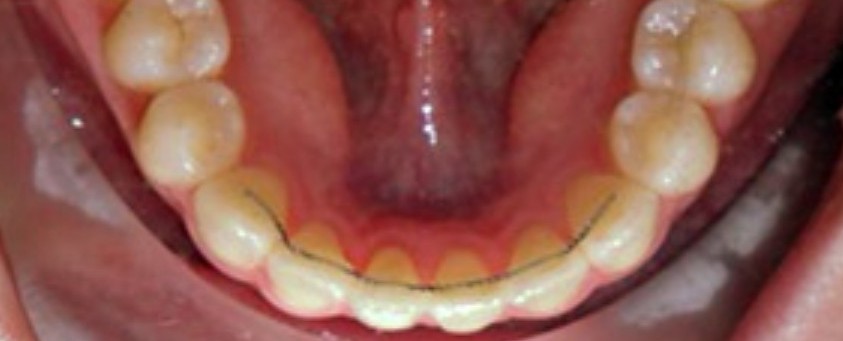

치아교정이 끝나고 장치를 제거하면 제거하는 그 순간 부터 치아가 예전으로 돌아갑니다. 즉 유지장치를 안하면 예전처럼 다시 비뚤비뚤해지니 약간은 불편하더라도 유지장치는 무조건 하는게 좋습니다.

교정장치 했을 때 만큼 많이 조심할 필요는없고 앞니쪽으로 아이스크림을 앙 물어먹거나 앞니쪽으로 단단한건 안드시는게 좋습니다. 유지장치가 앞니쪽에만 붙어있으니 어금니쪽으로 드시는게 좋겠죠???

유지장치는 항상 떨어지지 않도록 주의해주세요!!!!